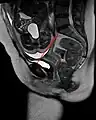

Conjugata vera as measured on sagittal MRI